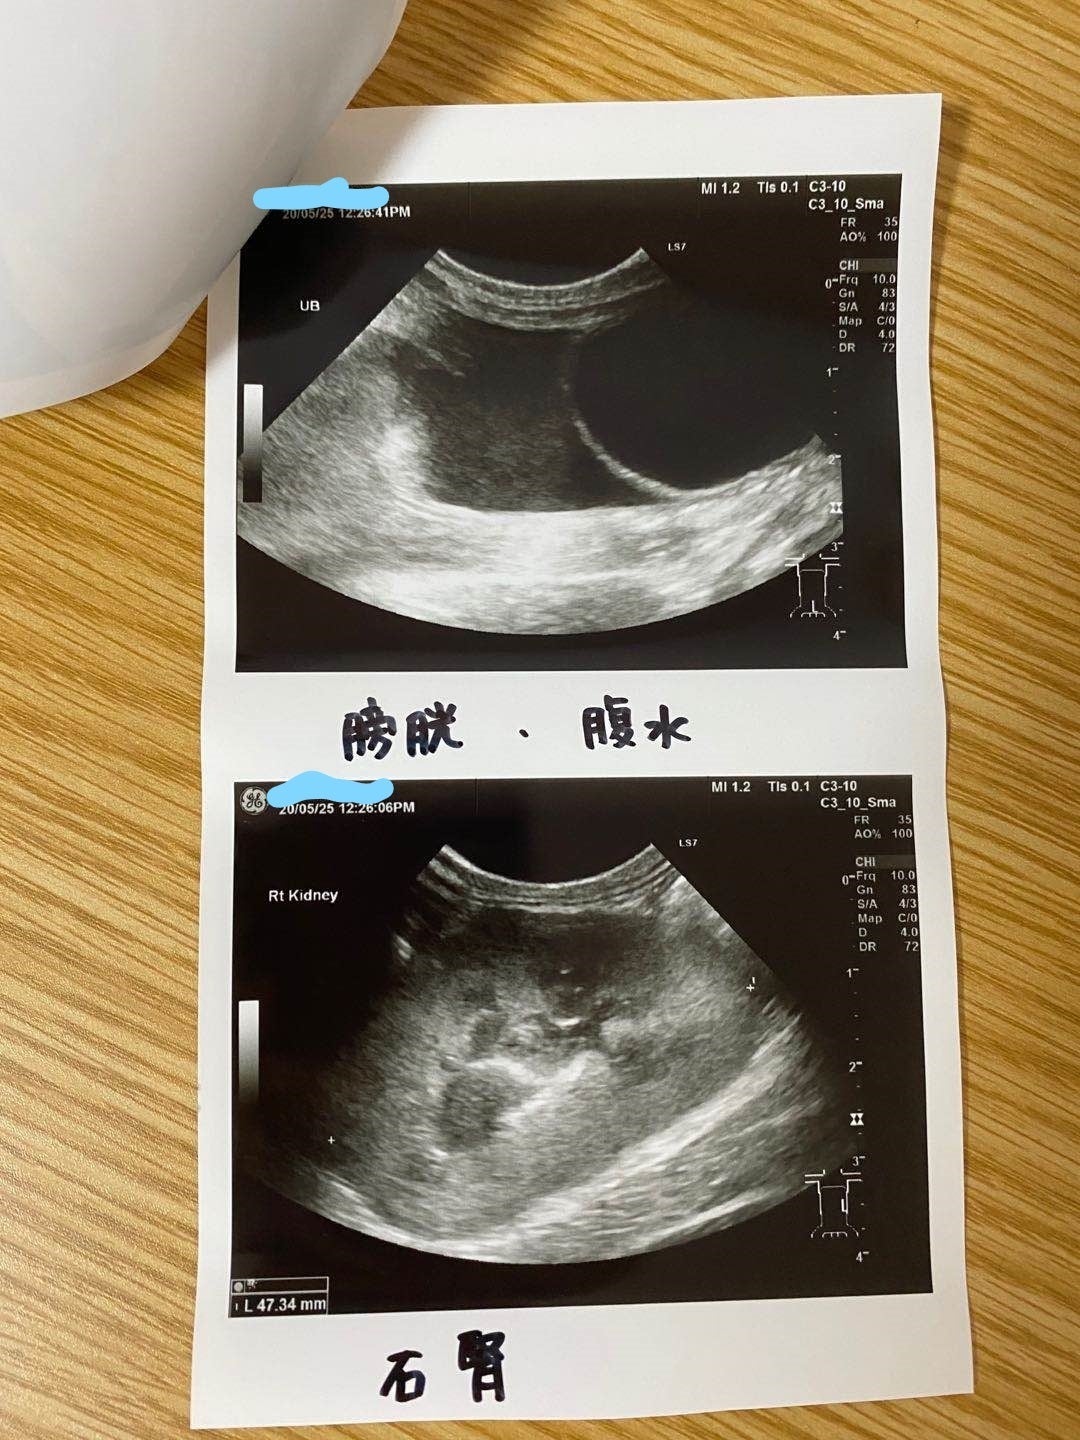

5/25家の近くの協力病院に行って、痛く辛い検査をして、中期混合型と診断されました。

腹水がたまっています

肉芽腫が見つかります